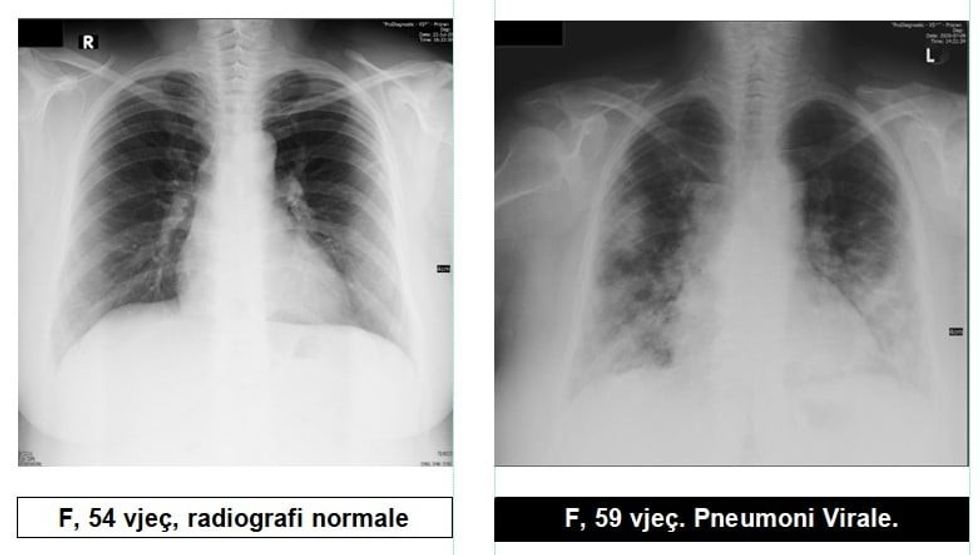

Radiologu Krasniqi tregon pamjet e mushkërive të pacientëve me COVID-19: Virus ka, pandemi ka dhe situata nuk është e mirë

Radiologu në Spitalin Rajonal të Prizrenit, Sylejman Krasniqi tregon pamjet e mushkërive të pacientëve me pneumoni virale.

“Për te gjithë ata që maskat i kane veç si dekorim, për ata që distancën sociale e kanë diçka të huaj dhe për të gjithë ata që nuk i respektojnë këshillat e institucioneve relevante Shëndetësore, këto imazhe le të ju shërbejnë që ta kuptoni se megjithatë virus ka, pandemi ka dhe situata nuk është e mirë”, ka shkruar Krasniqi, përcjell Telegrafi.